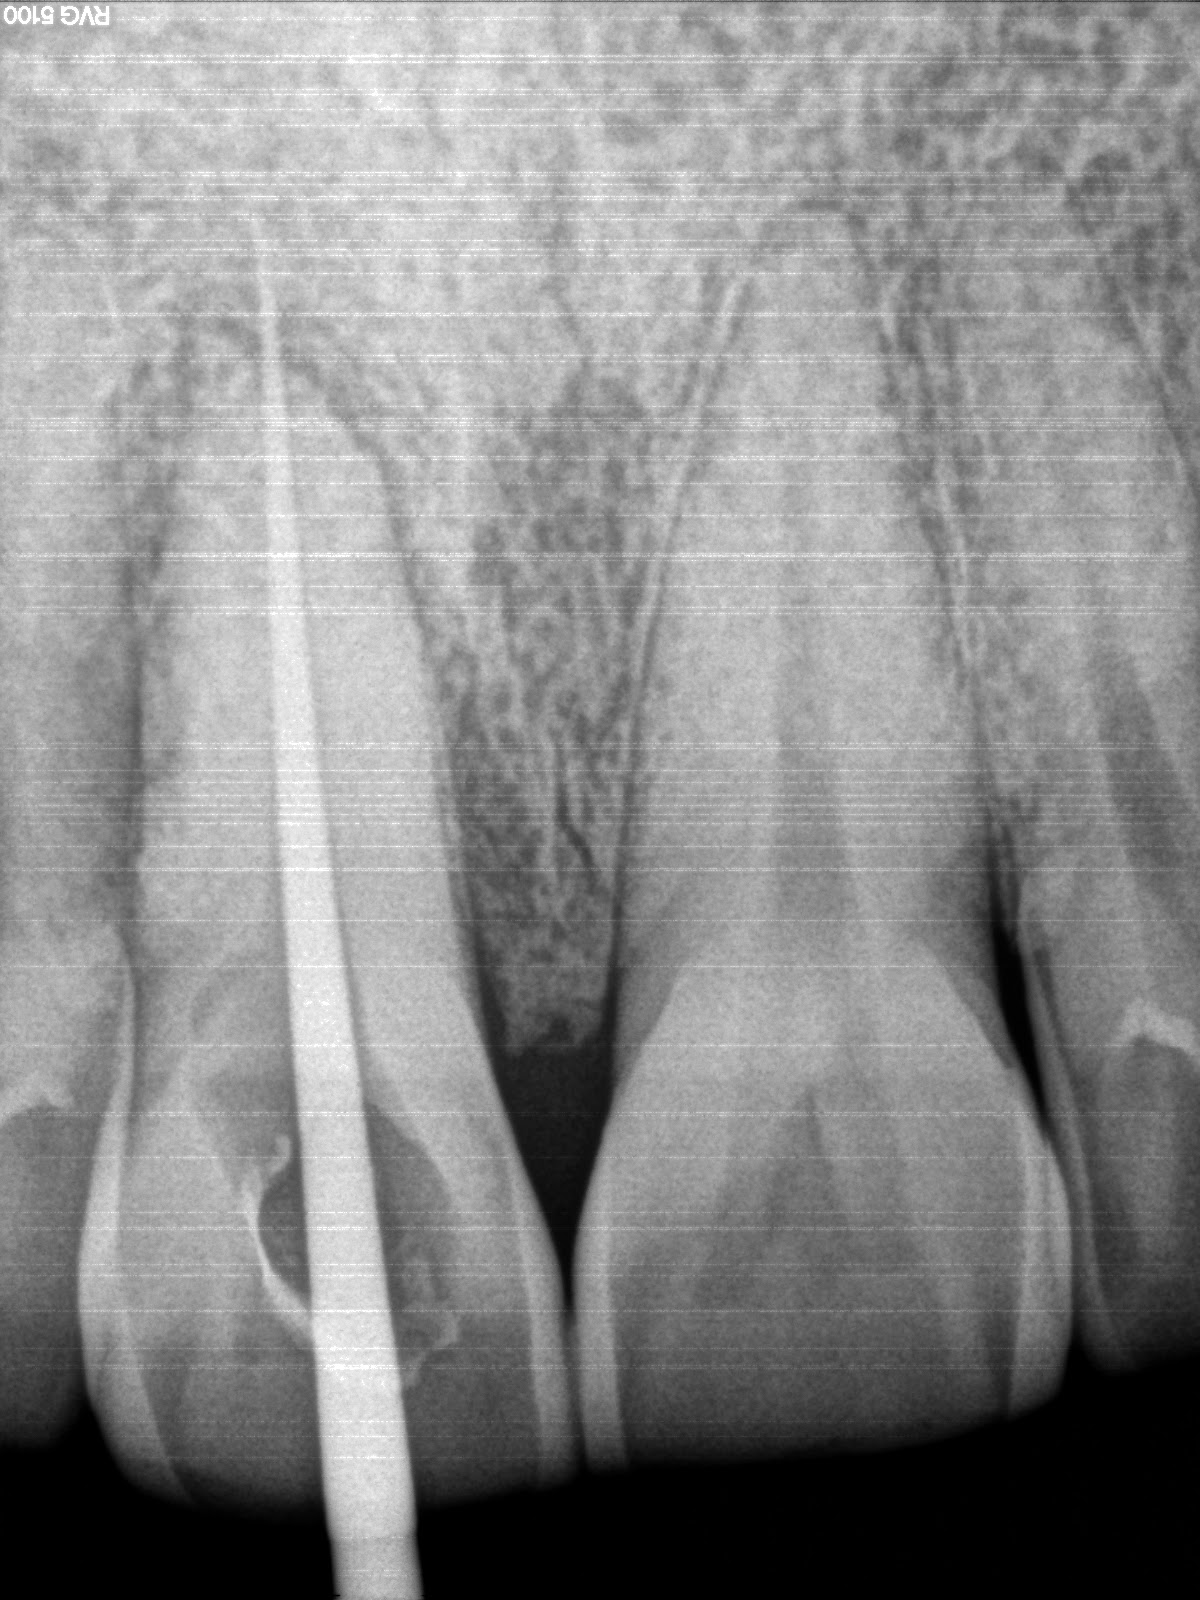

Guided endodontic access for root canal treatment for calcified Endodontic Treatment Central Incisor the present report illustrates the favourable outcome of root canal retreatment over a period of 24 years on a. the current case report enlightens the endodontic management of an anomalous maxillary left central incisor with two roots/root canals, a c. Removal of the roof of the pulp chamber and coronal pulp tissue. preparation of the tooth for. Endodontic Treatment Central Incisor.

Figure 2 from Guided Endodontic Treatment for Calcified Central Incisor Endodontic Treatment Central Incisor this article also focuses on the successful endodontic treatment of a. in the rare cases that present with a lesion around the apical fragment, a combined treatment. the objective of this paper was to present a case report illustrating the. Removal of the roof of the pulp chamber and coronal pulp tissue. preparation of the tooth. Endodontic Treatment Central Incisor.